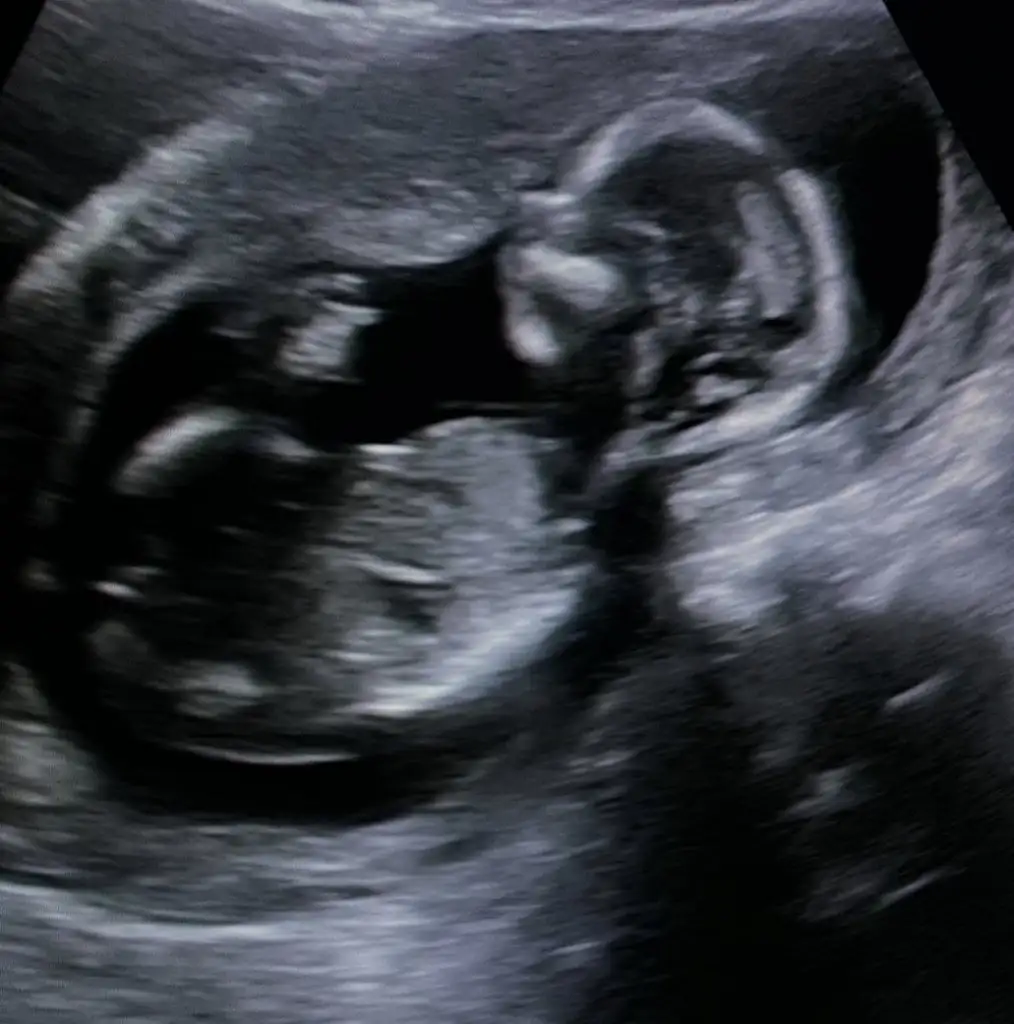

Buda ilk az once gonderdigim bugunkiydi 12 haftalik. Simdi attigim 7 haftalikValla hicbisey gormuyorum kese nerde gııı

Buda ilk az once gonderdigim bugunkiydi 12 haftalik. Simdi attigim 7 haftalik

Canim valla plesantan net degilEki Görüntüle 3073453

Bunda çok anlaşılmıyor gibi ama video da var konumu böyle8 haftalık burada bebişim